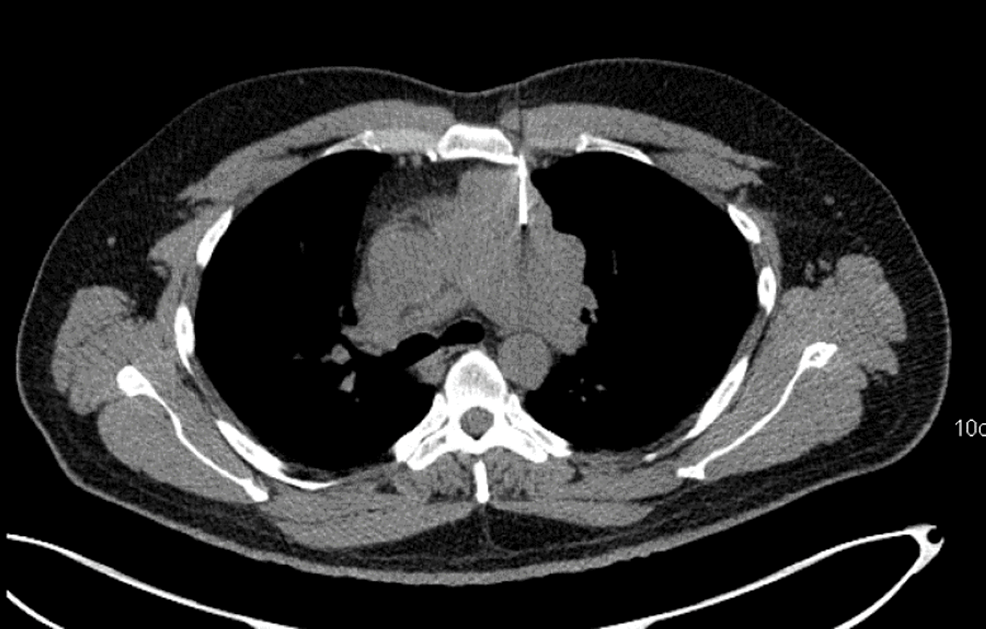

Thymic Lymphoepithelial Carcinoma A Rare Aggressive Mediastinal Mass Thymic Lymphoepithelial Carcinoma Primary thymic lymphoepithelial carcinoma is a rare neoplasm of the mediastinum. (1) micronodular thymic carcinoma with lymphoid hyperplasia (fig. Thymic lymphoepithelial carcinoma (tlec) is a primary thymic carcinoma that accounts for about 14% of all thymic epithelial. In the who 2021 classification, thymic carcinoma includes the following new subtypes (): Thymic carcinoma (tc) is a rare thymic epithelial neoplasm (ten). Thymic Lymphoepithelial Carcinoma.

Thymic Lymphoepithelial Carcinoma A Rare Aggressive Mediastinal Mass Thymic Lymphoepithelial Carcinoma Thymic carcinoma (tc) is a rare thymic epithelial neoplasm (ten) with heterogeneous features. Primary thymic lymphoepithelial carcinoma is a rare neoplasm of the mediastinum. In the who 2021 classification, thymic carcinoma includes the following new subtypes (): Thymic lymphoepithelial carcinoma (tlec) is a primary thymic carcinoma that accounts for about 14% of all thymic epithelial. (1) micronodular thymic carcinoma with. Thymic Lymphoepithelial Carcinoma.

Thymic Lymphoepithelial Carcinoma A Rare Aggressive Mediastinal Mass Thymic Lymphoepithelial Carcinoma Thymic carcinoma (tc) is a rare thymic epithelial neoplasm (ten) with heterogeneous features. In the who 2021 classification, thymic carcinoma includes the following new subtypes (): Thymic lymphoepithelial carcinoma (tlec) is a primary thymic carcinoma that accounts for about 14% of all thymic epithelial tumors and is classified into. Primary thymic lymphoepithelial carcinoma is a rare neoplasm of the mediastinum.. Thymic Lymphoepithelial Carcinoma.

Thymic Lymphoepithelial Carcinoma A Rare Aggressive Mediastinal Mass Thymic Lymphoepithelial Carcinoma Primary thymic lymphoepithelial carcinoma is a rare neoplasm of the mediastinum. (1) micronodular thymic carcinoma with lymphoid hyperplasia (fig. The recognition of clinical, radiologic, and. Thymic epithelial tumors (tets) are rare tumors, including thymoma, thymic carcinoma, and thymic neuroendocrine tumors. Thymic lymphoepithelial carcinoma (tlec) is a primary thymic carcinoma that accounts for about 14% of all thymic epithelial tumors and. Thymic Lymphoepithelial Carcinoma.